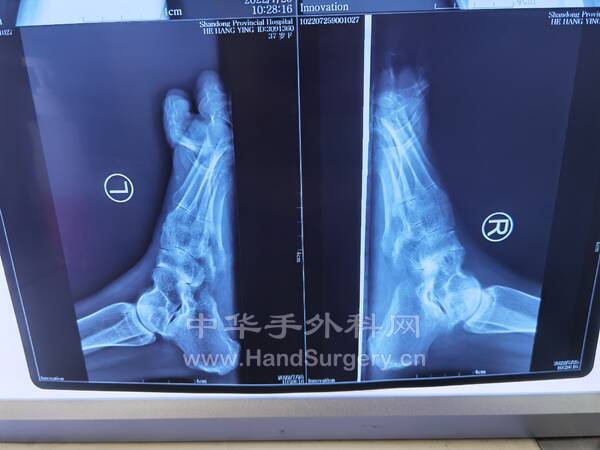

今日参观马蹄内翻足手术2台(图2-9第一个患者,10-17第二个患者)

4.第三腓骨肌的起止点与功能?(图1)

起于腓骨下1/3的前面及骨间膜,止于第5跖骨基底背侧面,作用为协助踝关节背伸(背屈)、足外翻及外旋。第三腓骨肌的肌腹与腓骨长短肌毗邻,其神经支配为腓深神经(L4-S2)。